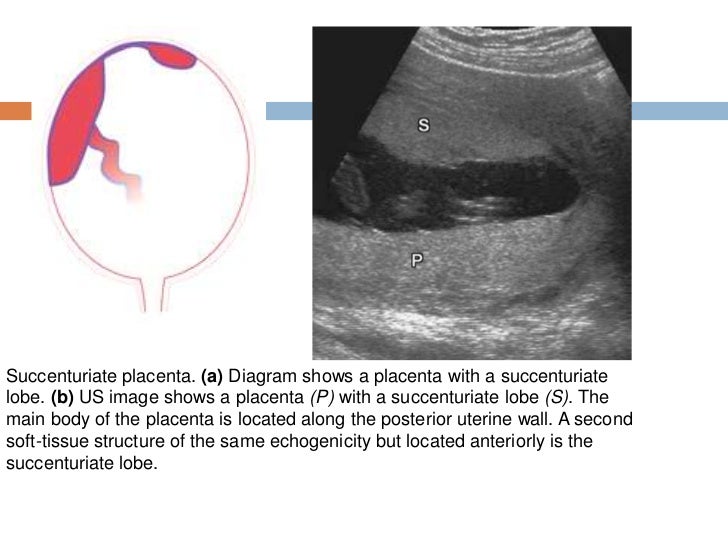

Succenturiate Lobe Placenta Ultrasound

Succenturiate Lobe Placenta Ultrasound What Is An Accessory Lobe On Placenta It is a small lobe of the placenta attached to the main disc. an accessory lobe of placenta is a variation in the normal shape of the placenta. The umbilical cord inserts into. two lobes of equal size, separated by fetal membranes or connected by narrow isthmus of placental tissue. placental magnetic resonance imaging (mri) has been. What Is An Accessory Lobe On Placenta.

Succenturiate Lobe Placenta Ultrasound What Is An Accessory Lobe On Placenta placental magnetic resonance imaging (mri) has been increasingly. two lobes of equal size, separated by fetal membranes or connected by narrow isthmus of placental tissue. It is a small lobe of the placenta attached to the main disc. a placenta containing three or more equally sized lobes is rare and termed multilobate. an accessory lobe of. What Is An Accessory Lobe On Placenta.